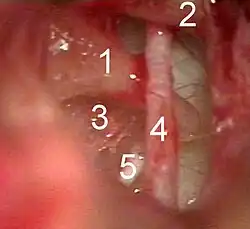

1 – Nervus vestibularis

2 – Nervus cochlearis

3 – Nervus facialis

4 – Ganglion geniculi

5 – Chorda tympani

Groß im Hintergrund das Trommelfell mit angewachsenem Hammergriff (im Bild HANDLE OF MAL.). Der Amboss ist der Übersichtlichkeit halber entfernt. Die Chorda tympani (im Bild CHORDA TYMPANI NERVE) kreuzt den Hammer zwischen Hammergriff und Hammerkopf (im Bild HEAD OF MALLEUS) und verläuft hier offen, wie eine Saite, in der luftgefüllten Paukenhöhle. Rechts im Bild der Abzweig der Chorda tympani vom Nervus facialis (im Bild FACIAL NERVE). Die Fasern der Chorda tympani verlaufen vom Abzweig gemeinsam mit den anderen Fasern des Nervus facialis nach oben (im Bild angeschnitten) zum Ganglion geniculi. Links der weitere Verlauf durch die Fissura petrotympanica (im Bild GLASERIAN FISSURE) ins Innervationsgebiet des Unterkiefers.